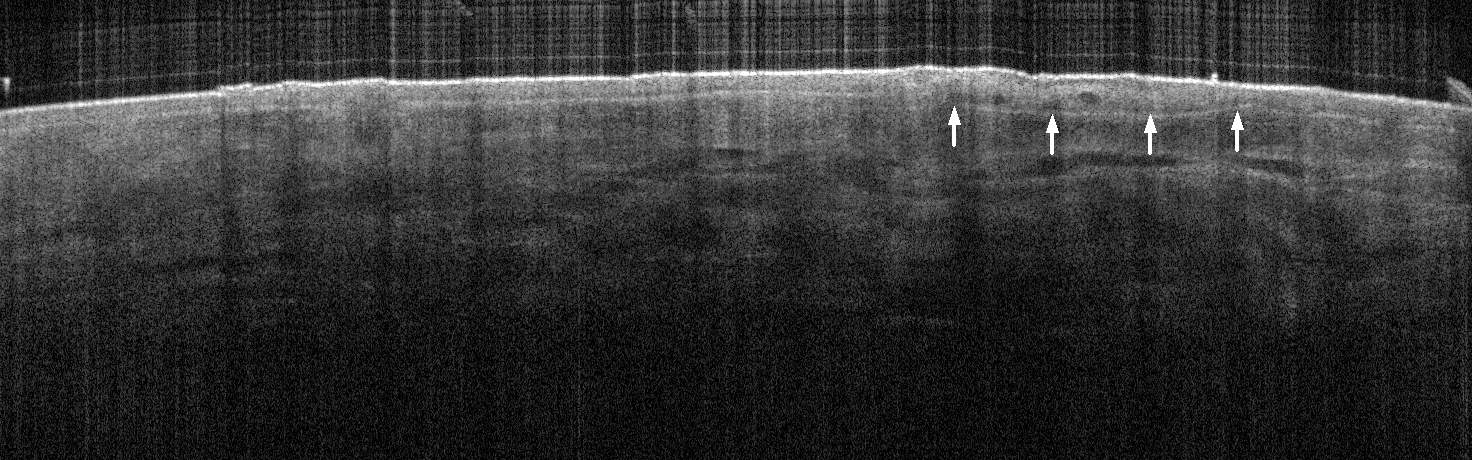

VA36: Upper Forehead, Left of Midline, Adjacent, Normal